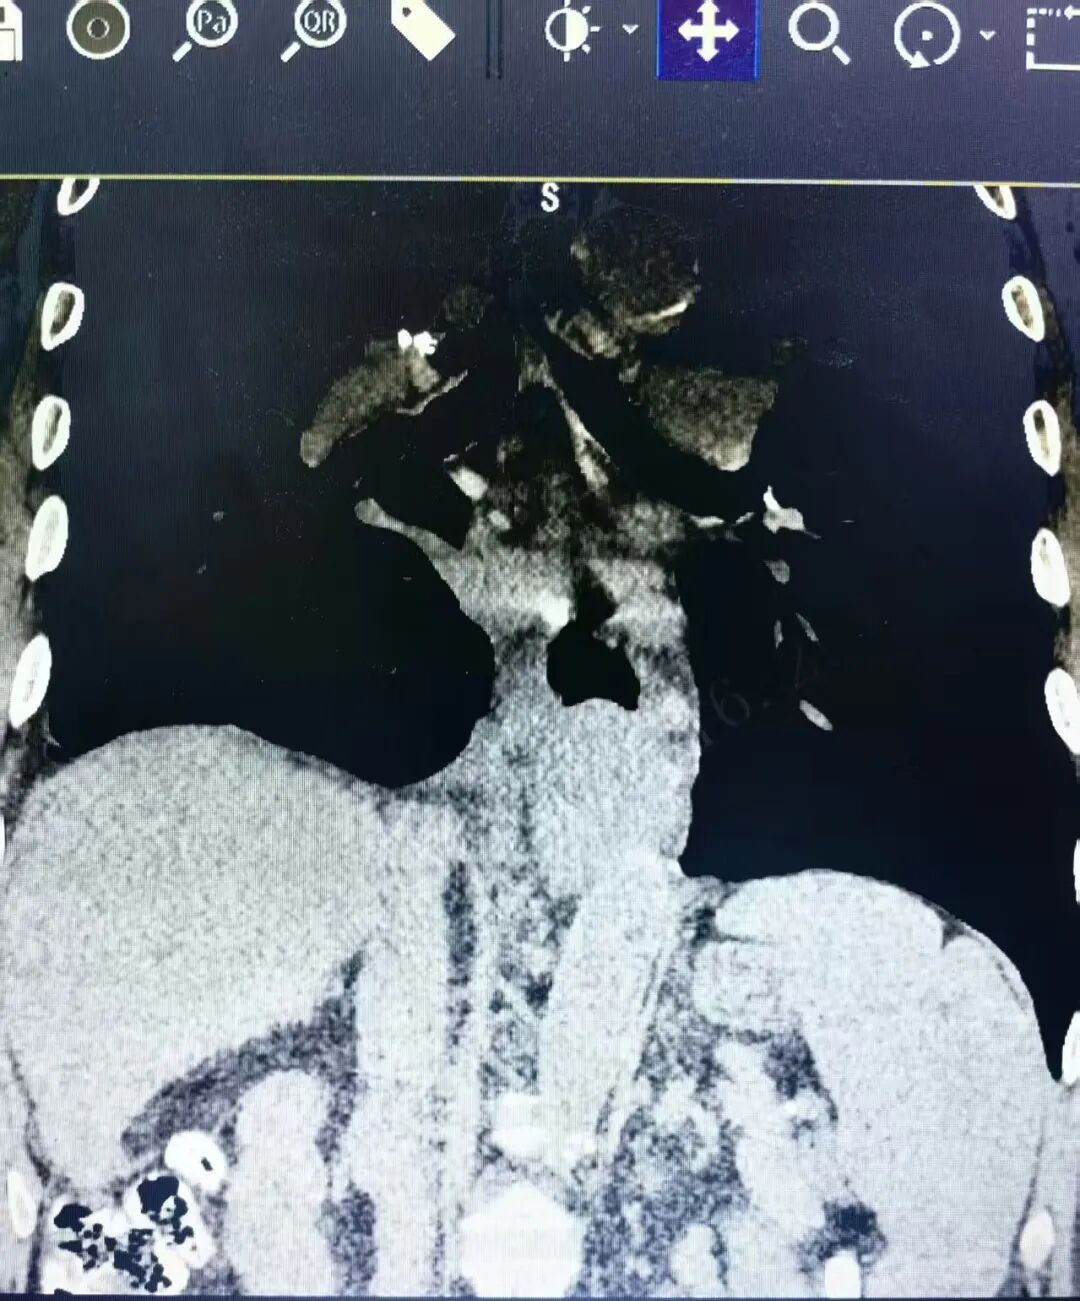

术前准备就绪后,手术按计划进行。术中探查可见:肝硬化导致食管下段及胃底周围静脉重度曲张,侧支循环丰富;脾脏因长期充血性肿大,质地脆嫩,与周围组织粘连致密。手术团队凭借娴熟的解剖技术与默契的配合,在完整切除食管肿瘤及清扫区域淋巴结的同时,成功游离并切除巨脾。术中出血量控制在650毫升,未发生难以控制的渗血,手术过程平稳。